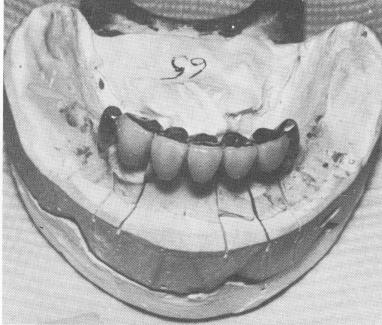

Fig. 12-59. The anterior fixed partial denture is fabricated with gold occlusals and acrylic facings.